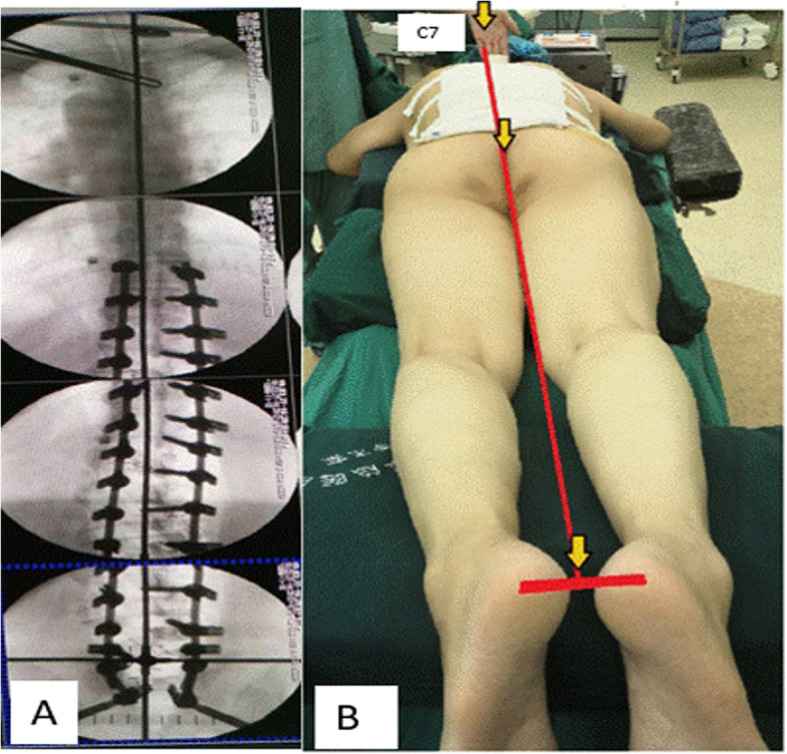

The inverted cross device was used at the final steps of the instrumentation. After the deformity was initially corrected, the inverted cross device was to be aligned on a patient (Fig. 2b). Its horizontal limbs were placed on the pelvis to align with supra-iliac line and shorter vertical limb in line with CSVL by using C arm. The longer vertical limb was then imaged fluoroscopically to check if it passed through C7 body (Fig. 3a). If it did, a well-balanced body would be obtained (Fig. 3b); If it did not, further maneuvers such as in situ coronal bending of the rods, compression, and distraction were performed to improve spinal deformity correction until C7 body was crossed.